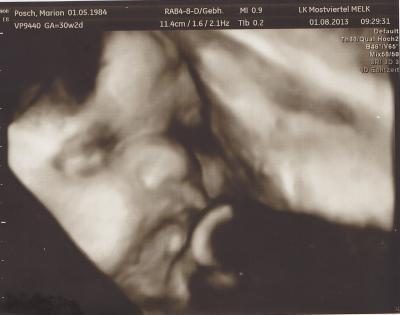

Waren ja heute in der Klinik bei der Nachkontrolle (Herzultraschall) vom Organscreening! Alles ist Bestens! Outing Junge wurde noch ein Mal zu 100% bestätigt! Herzchen ist gesund, alle großen Gefäße da wo sie hin gehören! Plazentaversorgung und Nabelschnurdurchblutung ist spitze! Fruchtwasser ist in Ordnung! Unser kleiner großer Mann wiegt jetzt 1760g, lt. Arzt völlig normal entwickelt, ist also jetzt keine Woche mehr vorn sondern jetzt genau termingerecht. Ein süßes Foto gibt es auch, allerdings wollte unser kleiner Plazentakuschler uns nur einen Teil seines Gesichtes zeigen :-) hütet sein Geheimnis weiter :-) Hab mich vom Zuckertest immer noch nicht ganz erholt, Kreislaufprobleme, Schwäche und das Essen klappt irgendwie nicht mehr so wie vorher, hab bereits wieder ein 1/2 kg abgenommen bei meiner bisher bescheidenen Zunahme von 1 kg leider die Hälfte. Naja, hoffe es wird bald wieder alles normal! Hoffe euch geht es gut und ihr findet ein schattiges Plätzchen bei der Hitze! LG Diana

Bild zu Bericht vom heutigen Termin! mit Bildchen :-) - Forum für Oktober - Mamis